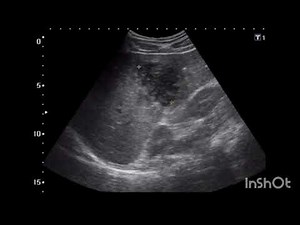

Understanding Pyogenic Liver Abscess Through Ultrasound Ima

…

Ultrasound Abdomen: Pyogenic Liver Abscess in Right Lobe – Cla